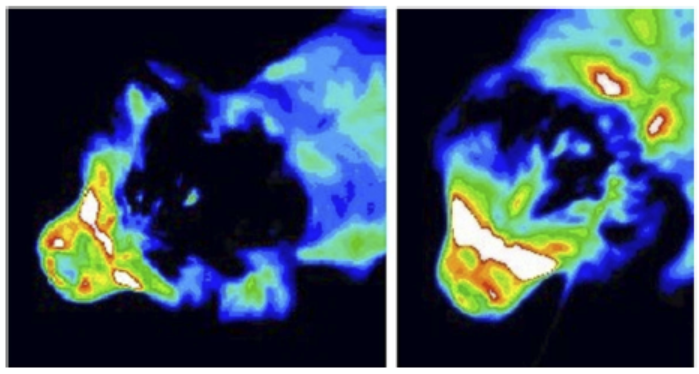

In an

October 2021 article, Drs. Srdjan Cirovic and Clare Rusbridge report

on a computer model they devised

which may explain how SM syrinxes (syringes) are created and expand, due to the impulsive movement of

cerebrospinal fluid (CSF), called "slosh". A magnetic resonance imaging

(MRI) scan of a cavalier was used as the model

design for the study. The investigators conducted simulations of various

spinal cord conditions, from the cord being free of cavities to small

syringes at different locations to a prorgessively expanding syrinx.

(See Figure 2.)